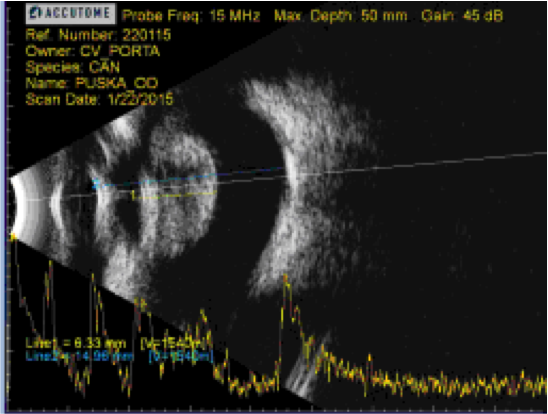

Se puede apreciar la diferencia significativa de un ojo microftálmico como es el de Tommy y uno de otro paciente, con un tamaño ocular normal pero también con hiperecogenicidad a nivel del cristalino debido a una catarata:

Los ojos microftálmicos tienen una longitud axial menor, por lo que no tienen las mismas dioptrías, un factor importante a la hora de querer que nuestros pacientes sean lo más próximos a un emétrope tras la cirugía de cataratas.

Debido a la microftalmia de Tommy, las lentes intraoculares (LIO) debían ser de 30 dioptrías (D).